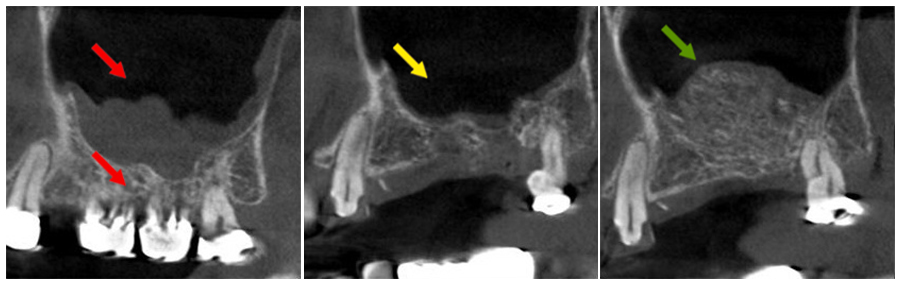

鼻竇破損後修補並進行上顎竇提升術之案例

病人於外院進行彈夾牙治療後牙根斷裂,合併鼻竇穿孔,鼻竇黏膜嚴重感染。

- 紅色箭頭:下方牙齒牙根斷裂,鼻竇黏膜感染增厚。

- 黃色箭頭:移除患齒後進行清創,拔牙後使用膠原蛋白修補,兩個月後恢復清澈鼻竇(影像區為黑色)。

- 綠色箭頭:鼻竇恢復健康後,進行上顎竇提升手術補骨,恢復上顎竇正常骨量,準備進行人工植牙手術。